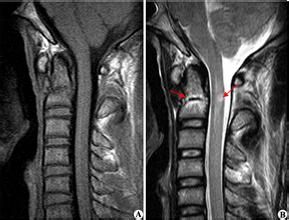

(2)室管膜瘤:好發年齡為40~50歲,可發生於脊髓任何部位以胸段和頸段最常見影像學表現與星形細胞瘤有一定程度的區別,腫瘤上端及尾端合併囊變是常見的標誌但腫瘤內囊變少見MRI為較均勻強化,或混雜信號部分病例腫瘤可突出至脊髓表面甚至達蛛網膜下腔。

(3)血管網織細胞瘤:不常見,有報導占脊髓腫瘤的2%均發生在髓內分兩種類型:①完全位於脊髓髓內中心;②軟膜性腫瘤部分突出到脊髓表面。腫瘤好發於30~50歲成人,男性多見常常發生於von Hippel-Lindau病。von Hippel-Lindau病中5%合併脊髓血管網織細胞瘤,36%~60%合併顱內血管網織細胞瘤。髓內血管網織細胞瘤常合併脊髓空洞症。腫瘤多有囊有報導,腫瘤有囊或病變上下脊髓增粗者占67%。影像學表現為囊性病變壁上有結節T1為邊界清楚的低信號,T2為高信號,增強可見腫瘤結節明顯強化。

(1)室管膜瘤:起源於脊髓中央管的室管膜細胞,於脊髓中央向外膨脹性生長,呈紫紅色或灰紫色,質地較軟,多數血液循環不豐富,與正常的脊髓之間有清楚的分界,多占據3~5個脊髓節段,腫瘤的上極或下極或兩極常有囊腫存在,通常可全切。

(2)星形細胞瘤:成人髓內星形細胞瘤多偏於脊髓一側生長,多呈黃色或灰色,與正常脊髓組織無明顯界限,低度惡性者血運不豐富,惡性者血運豐富,成人者全切率很低;兒童和嬰幼兒髓內腫瘤以星形細胞瘤占首位,常有瘤囊,實體部分位於囊內者全切率高。